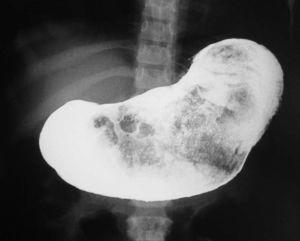

Ante el diagnóstico clinicorradiológico de tricobezoar gástrico secundario a pica, se realizó extirpación del mismo mediante laparotomía (fig. 2). Además, se inició dieta exenta de gluten y tratamiento sustitutivo con hierro.

Figura 2. Extirpación completa del bezoar que ocupaba la totalidad del estómago y se extendía a duodeno y porciones distales de yeyuno.